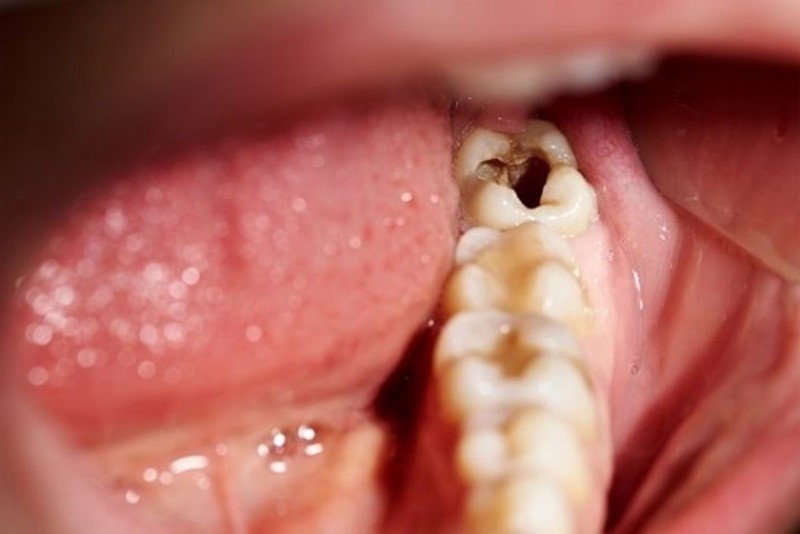

Đây là giai đoạn nghiêm trọng của bệnh lý. Men răng và ngà răng đã bị ăn mòn. Vi khuẩn gây sâu răng sẽ tiếp tục thâm nhập vào tủy răng có thể gây viêm tủy, viêm nướu và thường xuất hiện những cơn đau răng dữ dội.

Trên cung hàm không phải bất kỳ kẽ răng nào bạn cũng có thể nhìn thấy được đặc biệt là các kẽ răng ở hàm trên. Vì vậy, khi mắc sâu răng bạn sẽ rất khó phát hiện ra và bỏ qua thời điểm lý tưởng nhất để chữa trị. Sâu răng để càng lâu chúng sẽ càng làm nghiêm trọng thêm bệnh lý và dẫn đến nguy cơ mất răng rất cao.

(Bị sâu kẽ răng hàm thường rất khó phát hiện nên rất dễ gặp các biến chứng nguy hiểm)(**)

Viêm tủy răng là biến chứng thường gặp của bệnh sâu kẽ. Khi buồng tủy bị viêm nhiễm sẽ gây đau nhức răng dữ dội, nướu răng cũng có thể bị sưng viêm.

Viêm tủy răng nếu không được khắc phục vi khuẩn sẽ tấn công đến chân răng, cuống răng gây áp xe ổ răng. Bạn có thể nhận biết tình trạng này thông qua các nốt mủ xuất hiện dưới chân răng kèm theo những cơn đau nhức thường xuyên.